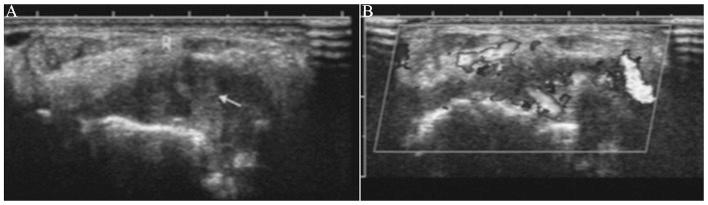

The aim of the present study was to explore the use of high frequency color Doppler ultrasound to measure synovial thickness and blood flow to assess the therapeutic value of the recombinant human tumor necrosis factor (TNF) II receptor antibody fusion protein in rheumatoid arthritis (RA) treatment. A total of 36 clinically-diagnosed patients with RA were treated with methotrexate tablets or the recombinant TNF-receptor antibody fusion protein for 24 weeks. Joint synovial thickness and synovial blood flow integrity were monitored by high frequency color Doppler in the second metacarpophalangeal joint in one hand. The correlation of the erythrocyte sedimentation rate, C-reactive protein (CRP) and 28-joint disease activity score (DAS28) with the ultrasound parameters were analyzed. Metacarpophalangeal second joint 2 (MCP2) synovial thickness, wrist joint synovial thickness and MCP2 synovial blood flow, prior and subsequent to the treatment, have a high correlation with DAS28 (P<0.05), and the MCP2 synovial blood flow integral has a strong correlation with CRP. Evaluating the wrist joint synovial thickness and synovial integrity of the second metacarpophalangeal joint using high frequency ultrasound detection can effectively evaluate the disease status in patients with RA. This procedure is potentially valuable as a means of evaluating the curative effects of RA treatments.